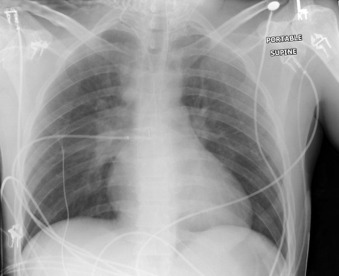

Central Venous Lines ( Figs. 22-1 to 22-13 )

To avoid mechanical irritation (from the catheter tip) and chemical irritation (from infusate) of the right atrium, the catheter tip of a central venous line should be further than the junction of the internal jugular vein and subclavian veins (near the level of the first thoracic rib). In addition, the tip should not be further in than the junction of the superior vena cava and right atrium. Central venous catheters that are intended to record central venous pressure should lie distal to the last venous valves (in the subclavian and internal jugular veins, 2.5 cm proximal to the beginning of the brachiocephalic vein) and before the right atrium. The ideal position of the tip of a peripherally inserted central catheter (PICC) line is in the distal superior vena cava.